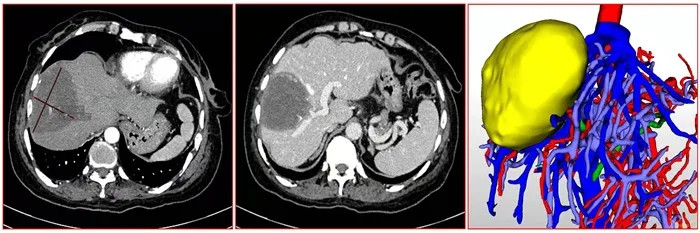

入院后肝膽外科經(jīng)CT、核磁共振檢查發(fā)現(xiàn)肝臟及盆腔有巨大腫塊,考慮肝臟包蟲病、盆腔包蟲病或盆腔畸胎瘤的可能。因病灶與血管關(guān)系密切,盆腔腫塊性質(zhì)待定,需多學(xué)科聯(lián)合會診決定治療方案。

肝臟包蟲病灶